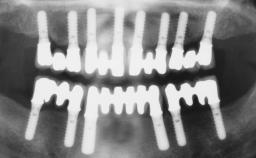

German Gallucci